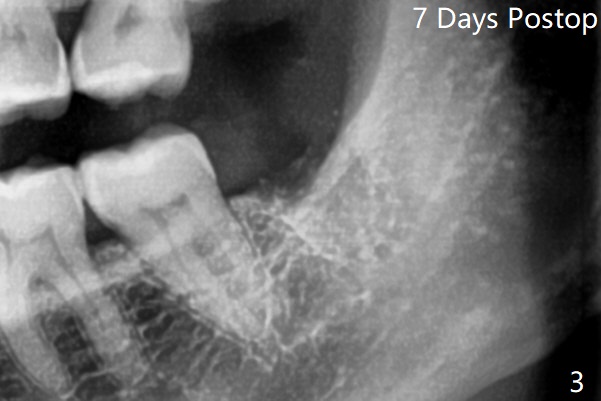

术前外斜脊(图一:*)存在,术后即刻没有消失,放置0.5毫升骨水泥(图二)。术后七天左下牙槽窝上部或者全部骨水泥丢失(图三)。